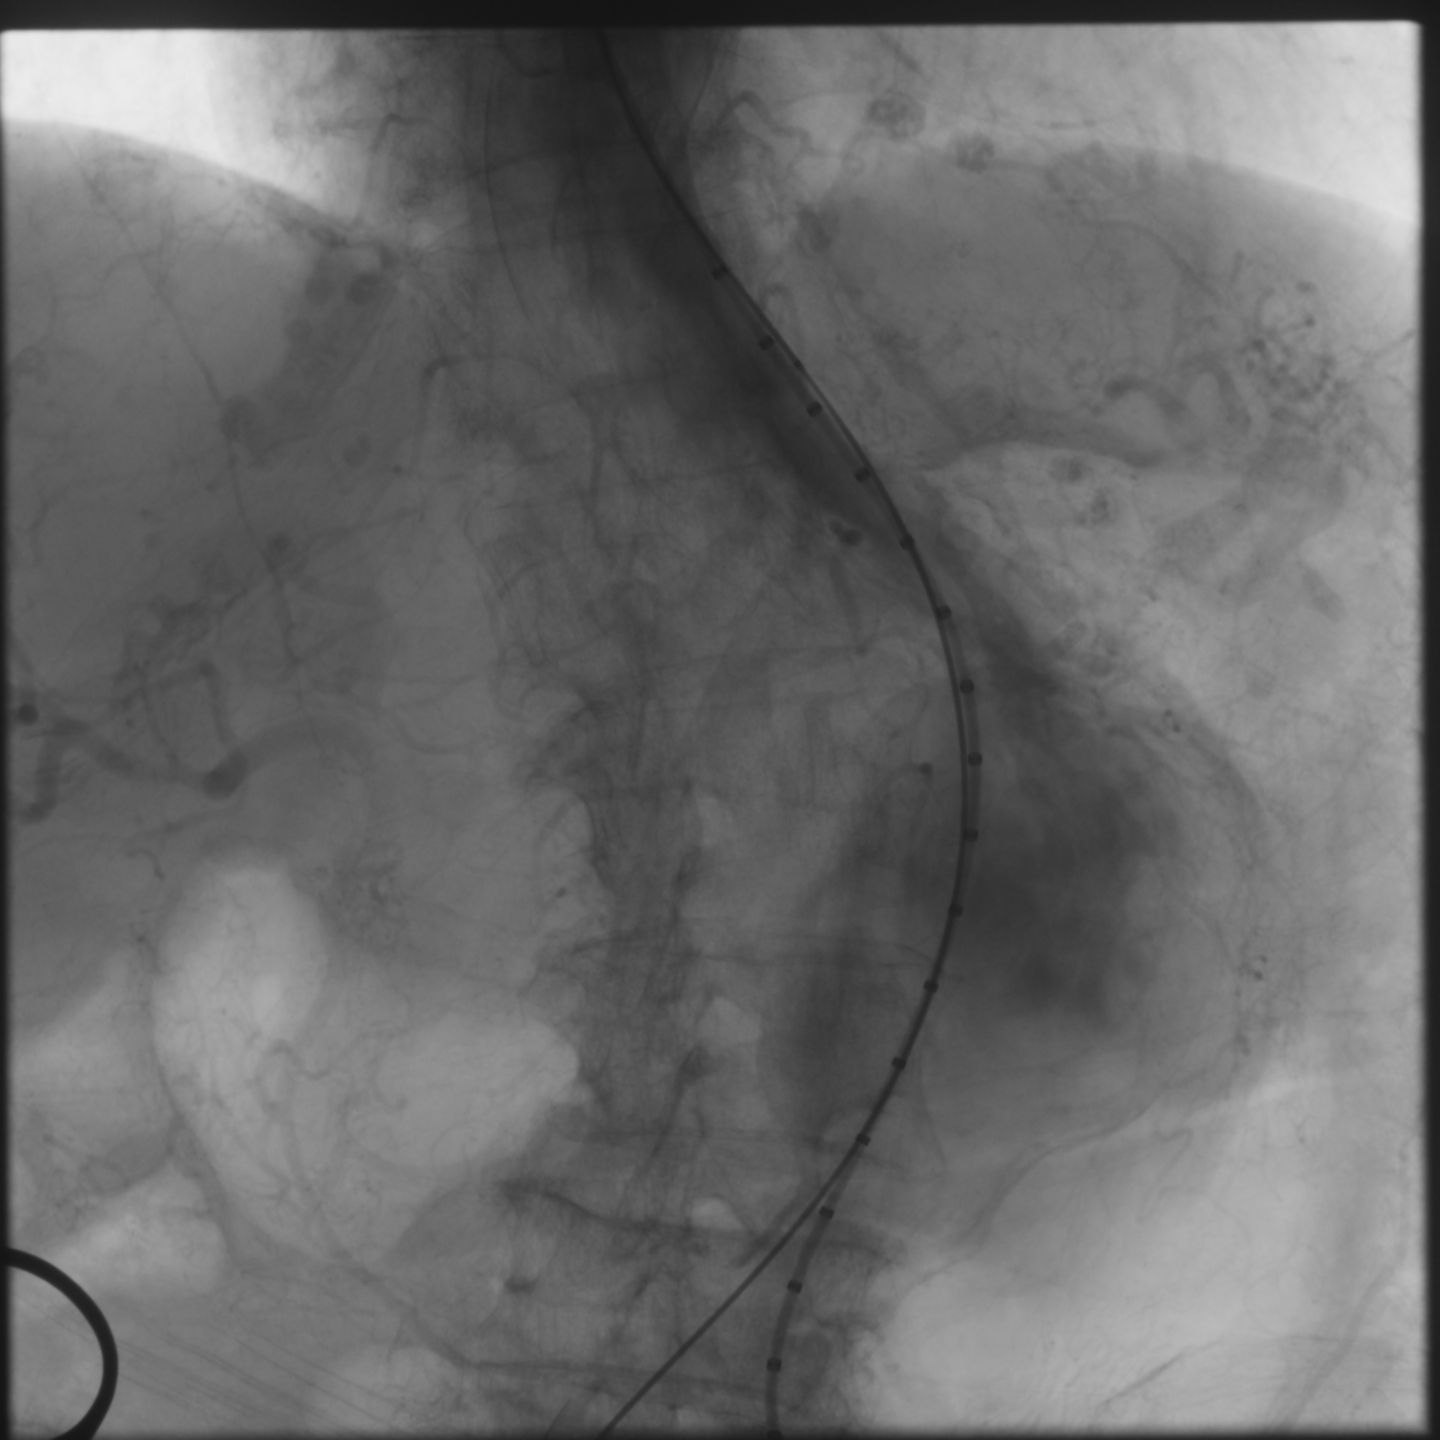

Percutaneous transluminal angioplasty (POBA) was performed on the proximal left common iliac artery using a 10 ¡¿ 80 mm Mustang balloon (Boston Scientific, USA) inflated and showing a balloon-waist formation consistent with a tight, fibrotic lesion. After gradual dilation up to 6 atm, the waist resolved and the lumen expanded, allowing smooth wire and sheath passage. The SEAL NOVUS stent-graft system (S&G Biotech, Korea) was used, with the main body (24 ¡¿ 50 mm) introduced via the right common femoral artery. Two flared iliac limbs, 12(18) ¡¿ 100 mm on the left and 12(16) ¡¿ 80 mm on the right, were deployed in a ballerina (crossed-limb) configuration to accommodate left-sided tortuosity and prevent kinking. During contralateral limb cannulation, angiography was performed within the main body to confirm the wire course inside the graft before advancing the sheath. Completion angiography demonstrated a Type Ia endoleak, treated with proximal neck flaring using a Coda LP balloon (Cook Medical, USA) under a rapid inflation–deflation technique to optimize sealing and prevent graft migration. Final angiography showed excellent proximal seal and bilateral flow, and follow-up CTA confirmed durable aneurysm exclusion without endoleak.